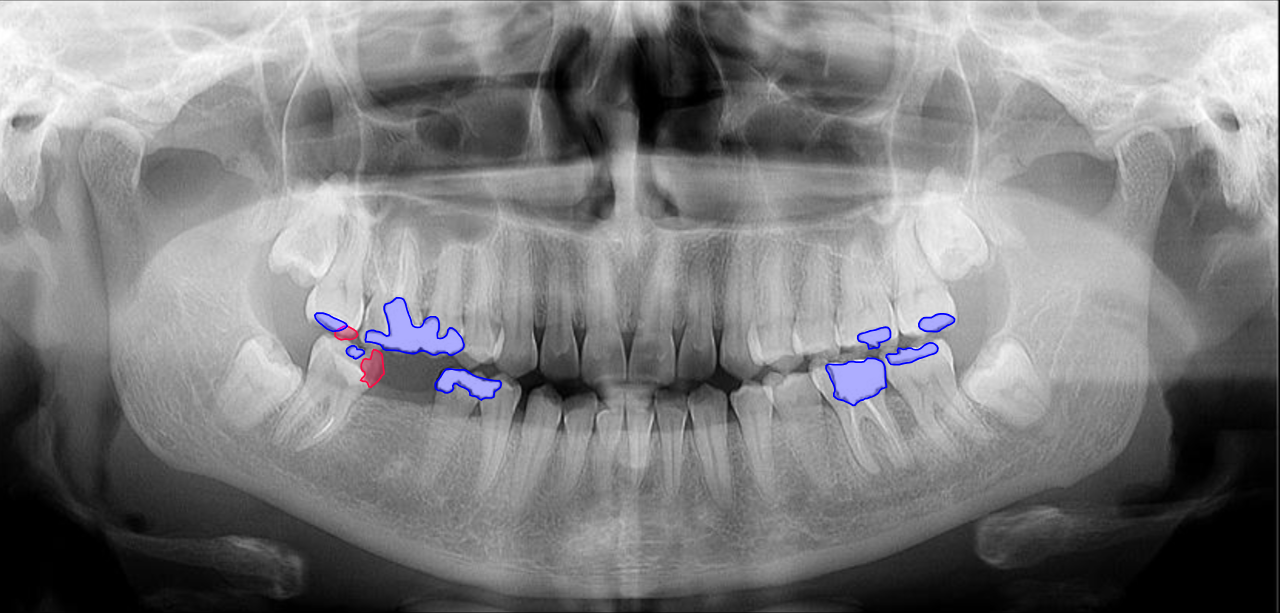

As the main product of Smartory startup, Smarteeth is a collaborative project with Shahid Beheshti Medical University, focused on developing an AI-powered assistant for diagnosing dental disorders using various radiography images (panoramic, bitewing, and periapical) and RGB images taken by mobile cameras. I was part of the core research and development team, where we collected and annotated over 100,000 radiography images and established a standard protocol for medical history and diagnosis forms in clinics. The AI tasks in this project include classification, detection, and segmentation of dental disorders, while Large Language Models (LLM) were used to generate basic diagnostic reports and basic suggestions based on the teeth condition. The project received significant attention at Exida, the International Congress of Dentistry, and has resulted in published research at the ICROM conference, with two more papers in progress. A free sample of our model is currently available on the Smarteeth website.